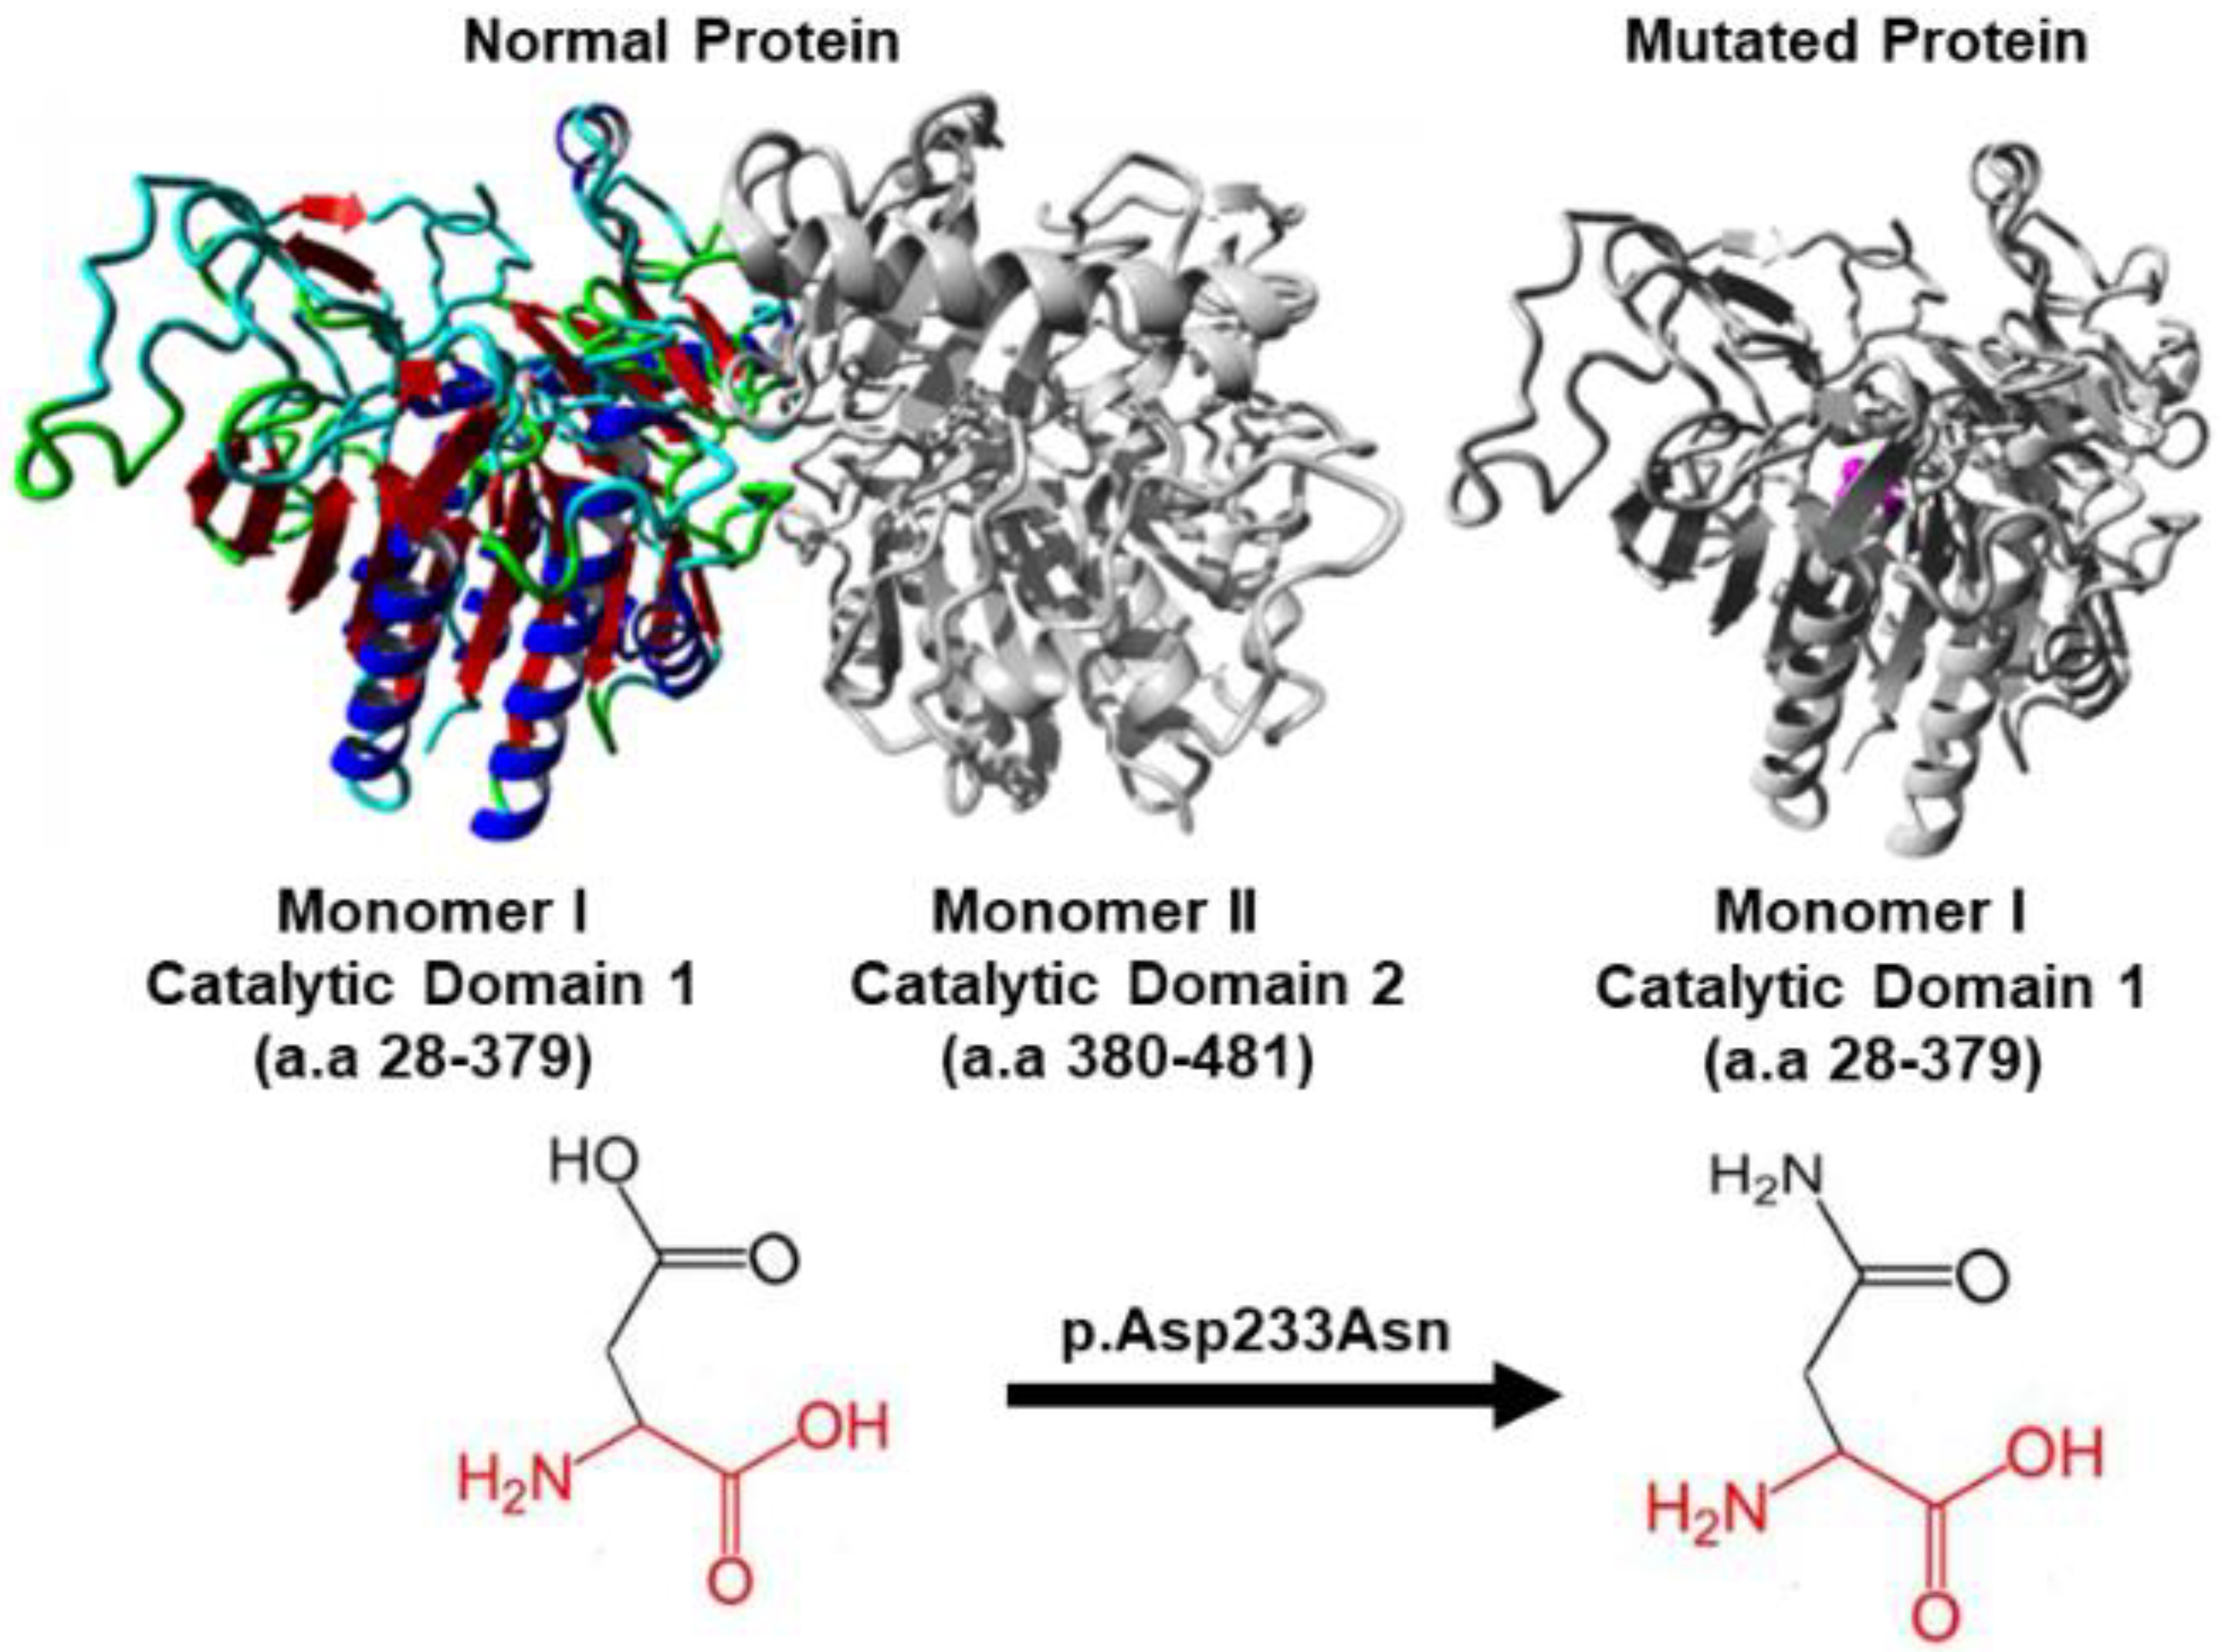

3.3. In Silico Protein Analysis